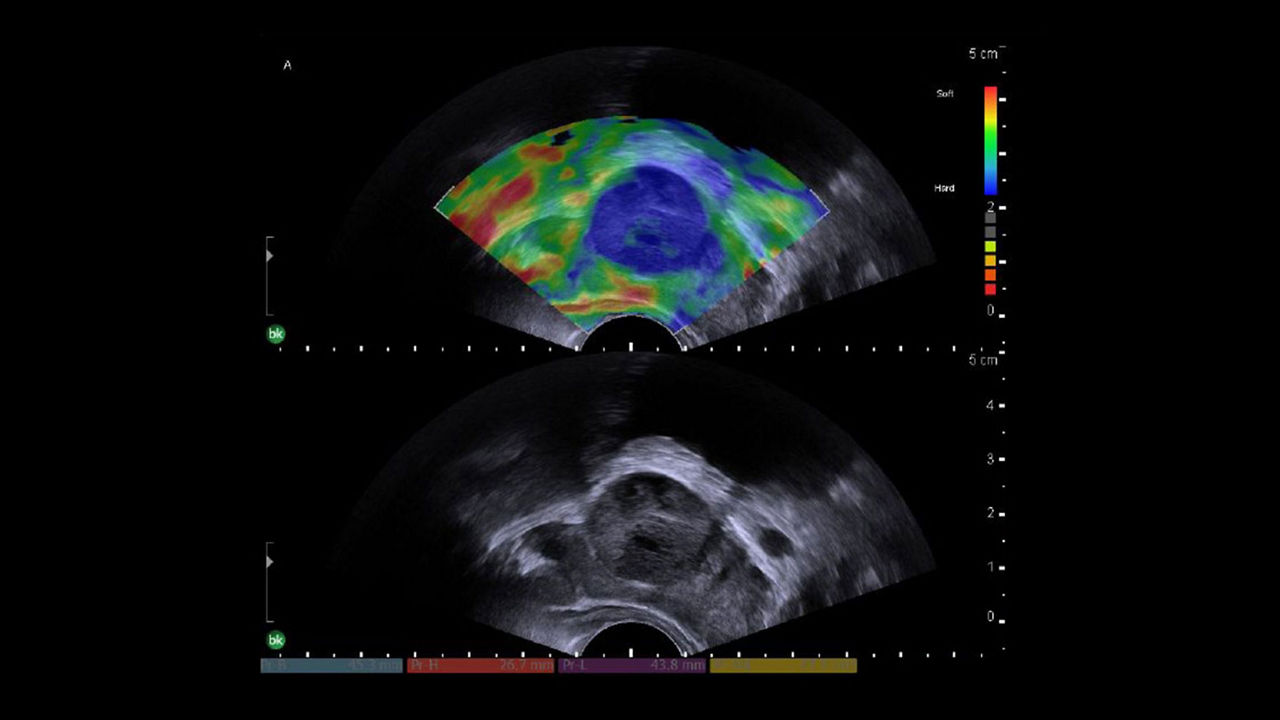

General surgery

Intraoperative ultrasound systems aid urinary tract procedures like cystoscopy and nephrolithotomy, improving visualization, accuracy, and surgical outcomes.

bkActiv Ultrasound System

The bkActiv ultrasound system offers advanced imaging for neurosurgery, urology, colorectal, and pelvic floor procedures. With enhanced resolution, customizable UI, and flexible monitor, it ensures precise, real-time guidance and improved surgical outcomes.